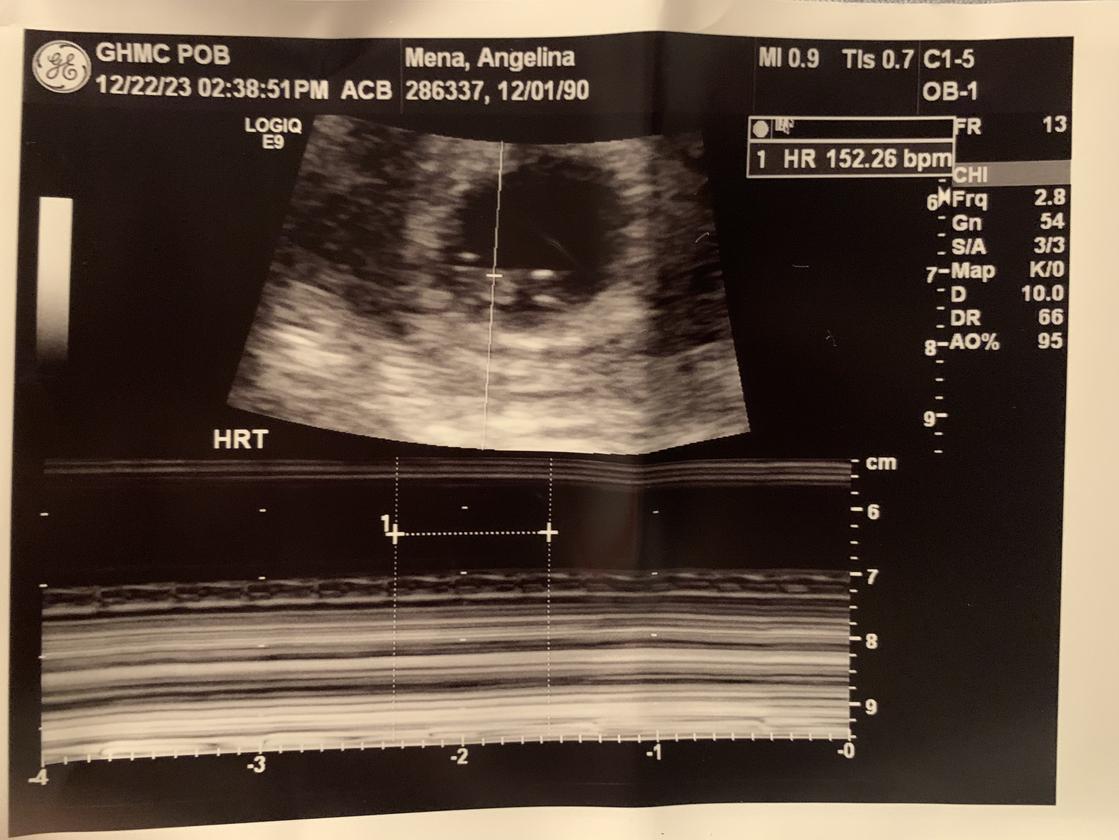

Skylar Castiel Cabrera-McGinn, affectionately known as Sky, was conceived in Monroe and tragically miscarried at the Westchester Medical Center in Valhalla, NY on December 30, 2023, at the tender age of 8 weeks and 5 days. Sky's gender identity unknown due to them being unborn the parents prefer for Skylar to be addressed using they/them pronouns.